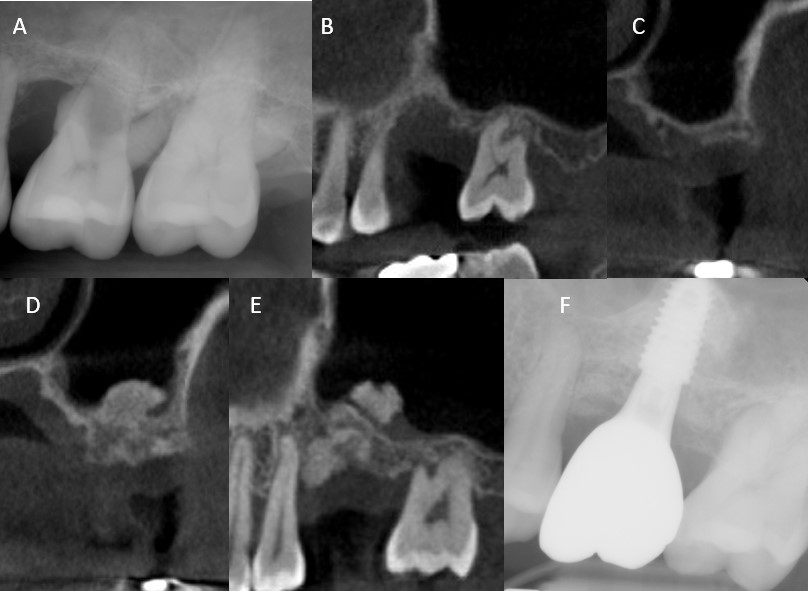

A 42-year-old male with generalized severe periodontitis underwent the extraction of a floating tooth 26 (Fig. 3A). At 4 months, CBCT revealed incomplete socket healing, with RBH < 1 mm (Fig. 3B and 3C). Transcrestal sinus floor elevation with simultaneous GBR was planned. Following full-thickness flap elevation and meticulous debridement of the compromised socket, the integrity of the Schneiderian membrane was confirmed using an osteotome. Subsequent membrane elevation was achieved using gentle hydraulic pressure with saline irrigation, followed by the insertion of 0.5 g of deproteinized bovine bone mineral (Bio-Oss; Geistlich Pharma AG) into the sinus cavity. GBR was performed in the extraction socket using the remaining Bio-Oss particles and a 250 mg block-type xenograft (Bio-Oss Collagen; Geistlich Pharma AG) and a resorbable collagen membrane (Bio-Gide; Geistlich Pharma AG), achieving tension-free primary closure.

Five months postoperatively, CBCT revealed dual-compartment bone regeneration, with a dome-shaped graft in the sinus and well-contained bone regeneration at the extraction site, yielding a total bone height of 9.5 mm (Fig. 3D and 3E). A dental implant (TS III, Ø4.5 × 8.5 mm; Osstem Implant) was placed with moderate initial stability, and a healing abutment was connected. ISQ measurements of 71/73 prompted an extended healing period, and prosthetic loading was initiated 6 months after placement. At the 38-month follow-up, the implant remained functional, with healthy peri-implant soft tissues and no complications (Fig. 3F).

Fig. 3

Radiographic sequence of Case 3. (A) Pre-extraction radiograph showing severe mobility of tooth 26, (B, C) Four-month post-extraction cone-beam computed tomography (CBCT) images reveal delayed socket healing, (D, E) Five-month postoperative CBCT demonstrating dome-shaped sinus graft and regenerated alveolar bone within the extraction socket, (F) Radiograph at 38-month follow-up showing a stable implant with healthy peri-implant tissues.